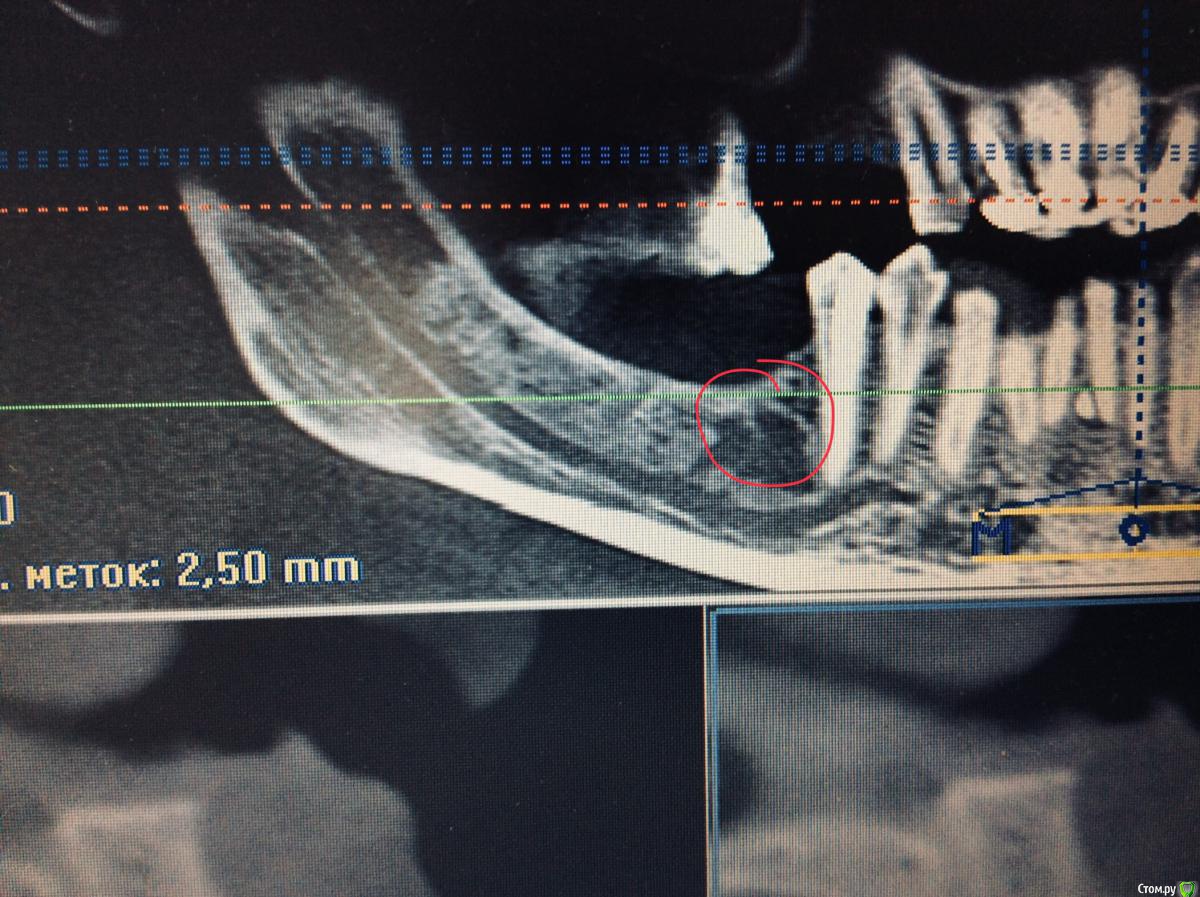

dr.Dre Опубликовано 11 мая, 2018 Поделиться Опубликовано 11 мая, 2018 Добрый вечер, что это может быть почему такая резорбция кости, можно ли поставить имплант а это место не провалюсь ли в нижьоальвеолярный нерв? Ссылка на комментарий

Aquarius Опубликовано 12 мая, 2018 Поделиться Опубликовано 12 мая, 2018 Ну скажем , внезапно в канал Вы не провалитесь. А это может просто строение кости такое. Там на снимке , ближе к венечному отростку, такая же пустота))) Ссылка на комментарий

колесников Опубликовано 12 мая, 2018 Поделиться Опубликовано 12 мая, 2018 Остеопороз Ссылка на комментарий